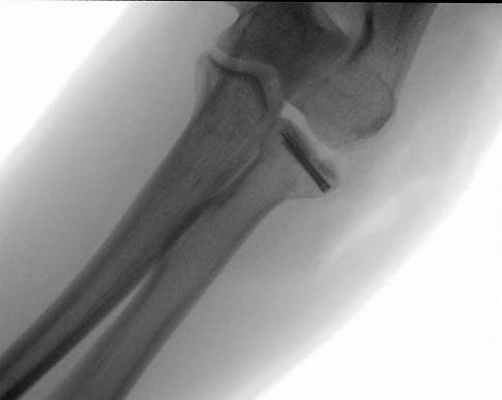

1. Реконструкция при помощи специальных винтов и пластин

Остеосинтез пластиной и винтами: Лечение перелома головки лучевой кости. © Gelenk Klinik

Фрактуры со смещением более 2мм (Тип 2 по формуле Мэйсона) лечатся как правило при помощи специальных винтов и микропластин. Данное вмешательство называется остеосинтез и является малоинвазивным.

Смещенный костный обломок возвращается в свое изначальное положение, где проводится его фиксация. Так хирург предотвращает образование ступеней на суставной поверхности. Используемые винты и пластины удалять необязательно. Их можно использовать для лечения сопутствующих повреждений связок.